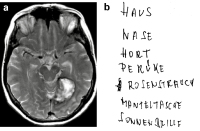

Kognitive Rehabilitation bei neurologischen Erkrankungen: Was ist anders? // What is unique cognitive rehabilitation? Though frequent sequels of neurological disorders, cognitive deficits are rarely diagnosed and treated adequately in routine care.